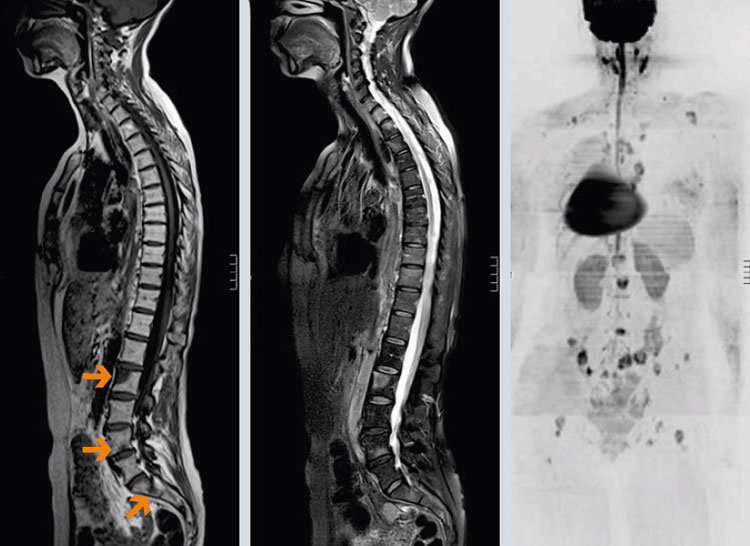

КТ и МРТ

Если сравнивать УЗИ с другими передовыми технологиями – КТ и МРТ, здесь тоже имеются отличия. Хоть по способу исследования (технологически) это новые методы, но они не настолько информативны, как ультразвук. Основаны компьютерные исследовательские методики на магнитном резонансе, и с их помощью можно оценивать состояние околопозвоночных тканей, дисков – преимущественно костной структуры. Состояние внутренних органов гораздо яснее может представить ультразвуковое изображение.

Кстати. С ультразвуком детально рассмотреть плотную костную структуру не получится, но проанализировать состояние мягких тканей он позволит как нельзя лучше. По итогам выполнения процедуры врач получит информацию о связках, соединительных и хрящевых структурах, суставах, дисковых сегментах и патологиях «притаившихся» там.

МРТ позвоночника

УЗИ-исследование даст возможность выявить остеохондрозные изменения, грыжевые образования, степени сколиотических искривлений и даже врожденные пороки развития позвоночных структур.